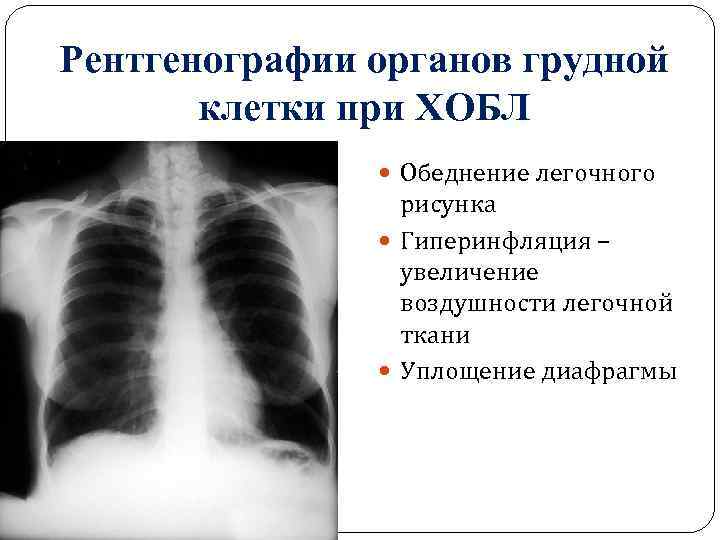

Ячеистая деформация легочного рисунка: медицинская визуализация